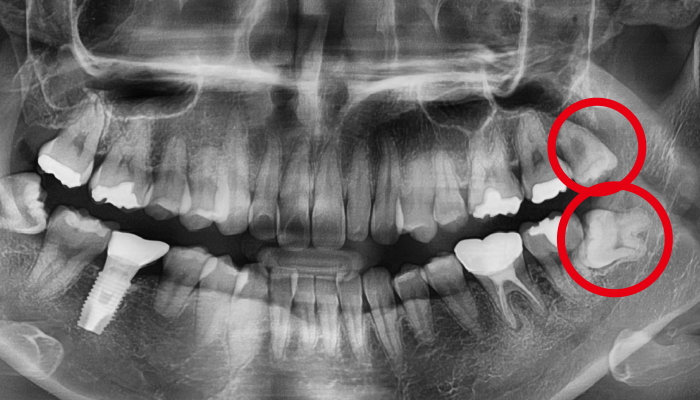

사랑니 발치 전후 사례

• 치료 전

치료 후